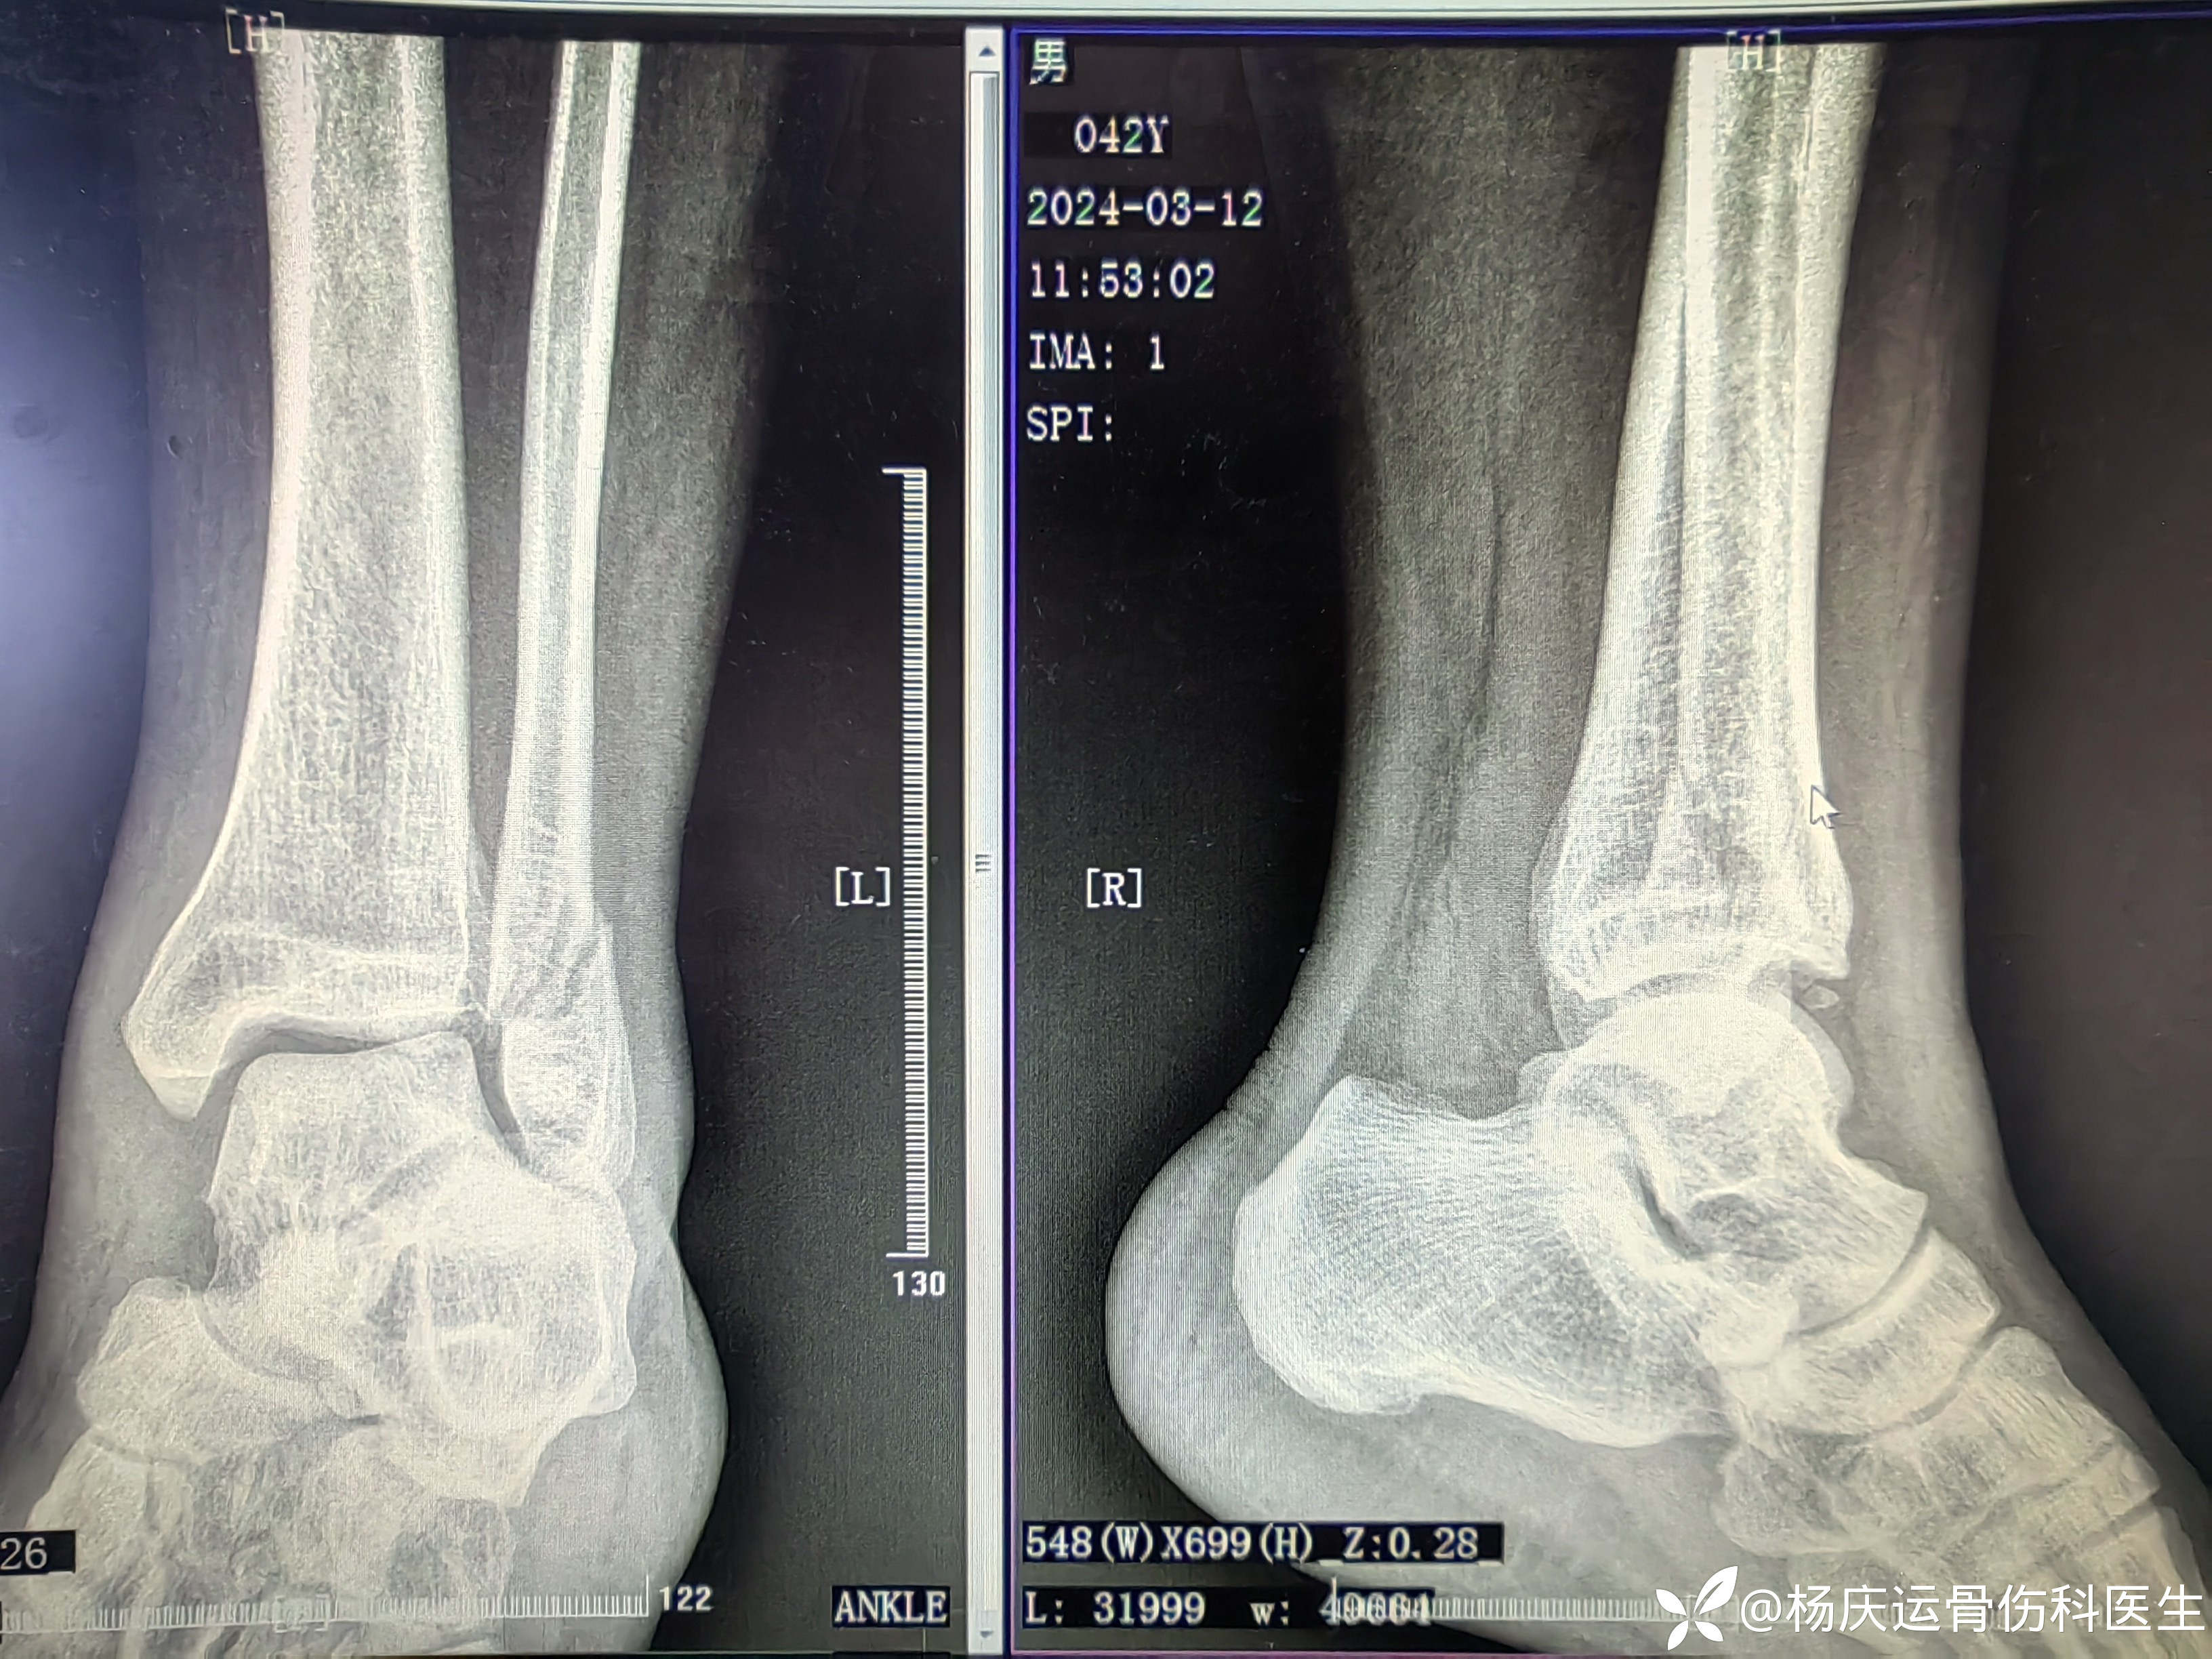

首诊片